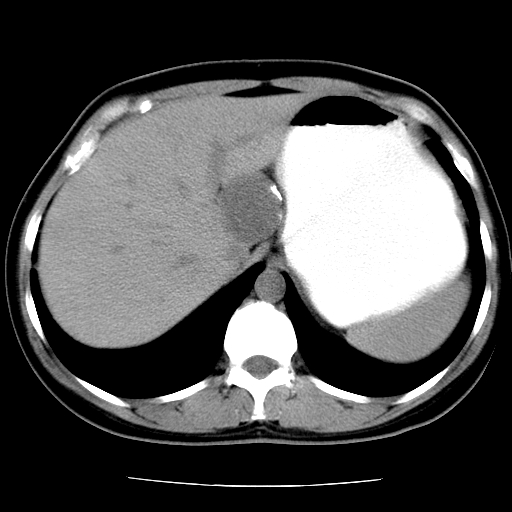

标题: CT16892:女40Y,急性阑尾住院!

女40y,急性阑尾住院!术前发现请会诊!

考虑门静脉瘤样扩张可能,建议增强扫描

胰头假性囊肿也有可能,建议增强

病灶位于门静脉的位置 ,有层面显示血管夹层样改变 ,考虑是门静脉瘤样病变1

病灶位于门静脉的位置 ,有层面显示血管夹层样改变 ,考虑是门静脉瘤样病变,建议进一步增强ct检查。

肝胃间隙良性占位病变,考虑囊肿可能性,不除外神经源性肿瘤,建议增强

肝门区囊性占位,壁有钙化,考虑良性。来源难定。